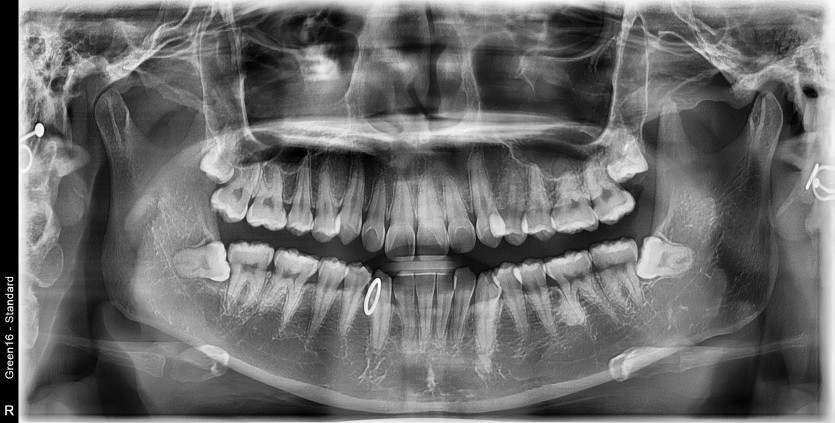

#48 사랑니 발치

구강 외과 전문의가 당일 발치했습니다.